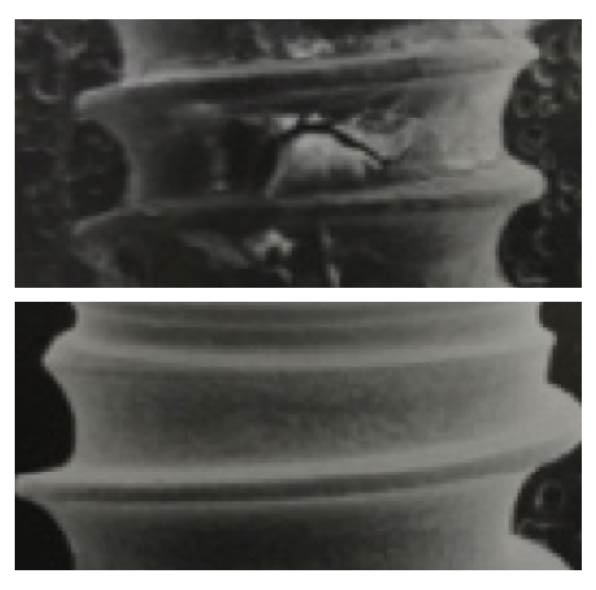

赤く示した部分の形態を作り替えて清掃性を良くする

以上、インプラント周囲炎の治療法を述べましたが、天然の歯の歯周病と比べて難易度は高い。その理由としては、インプラントは骨との結合を良くするために表面をあえて粗造にしてある。インプラント周囲炎に罹患してない時は問題ないが、一度罹患してしまうと骨が溶け、インプラントの粗造な表面が露出するので汚れが溜まりやすく、進行しやすい。

インプラント周囲炎は早めの対応をすることで、この粗造な表面が感染する前の軽度な状態で対応することが必要なので、定期的なメンテナンスが重要となる。